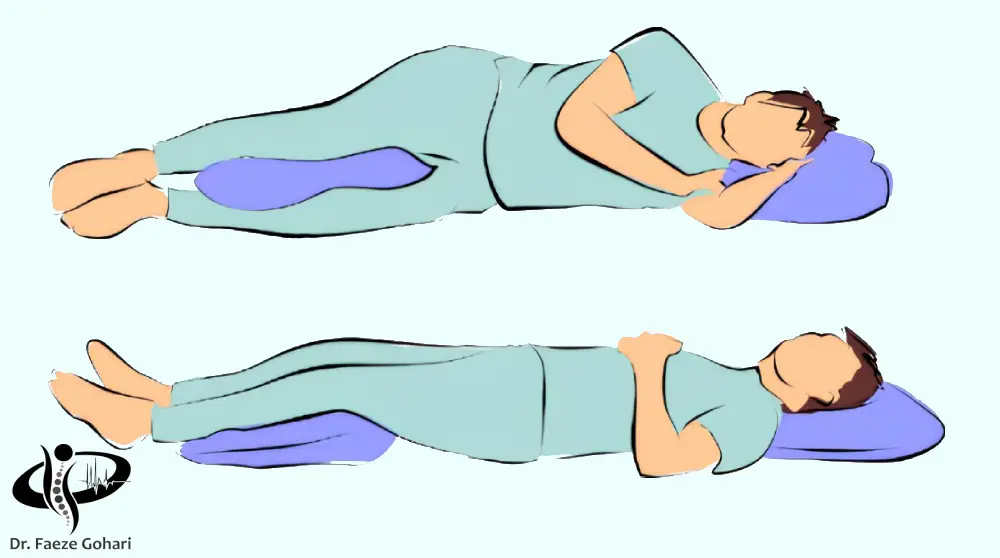

در وضعیت راحت و صحیح

استراحت مناسب یکی از نخستین و مؤثرترین اقدامات برای کاهش دردهای عضلانی کمر است. هنگامی که عضلات دچار کشیدگی یا اسپاسم میشوند، کاهش فشار مکانیکی و پرهیز از حرکات تشدیدکننده به آنها فرصت ترمیم و آرامش میدهد. با این حال، استراحت باید بهصورت کنترلشده و در وضعیت مناسب انجام شود تا از خشکی و تشدید درد جلوگیری گردد.

در زمان استراحت به نکات زیر توجه کنید.

- روی سطحی نسبتاً سفت دراز بکشید (نه بسیار نرم، نه بسیار سخت).

- به پشت بخوابید و یک بالش زیر زانوها قرار دهید تا انحنای کمر کاهش یابد.

- یا به پهلو بخوابید و یک بالش بین دو زانو بگذارید.

- مدت زمان استراحت باید کوتاهمدت باشد، معمولاً بین 24 تا 48 ساعت کفایت میکند.

- در طول روز، چند بار به مدت 20 تا 30 دقیقه در این وضعیت قرار بگیرید، اما از استراحت مطلق طولانیمدت پرهیز کنید.